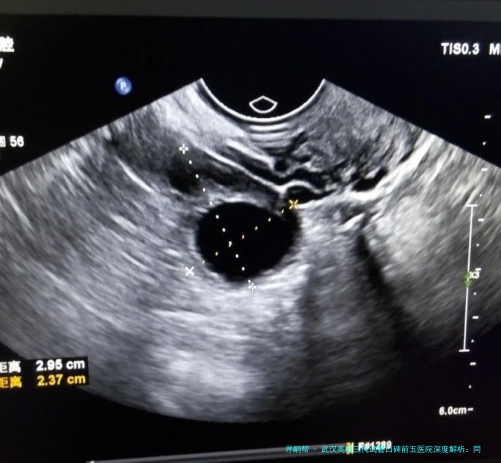

服务与配备:服务流程规范,预约系统相对完善。实验室配备有纺锤体察看仪等高端器械,有益于进行更精细的卵胞浆内单精子注射(显微受精技术)操作。